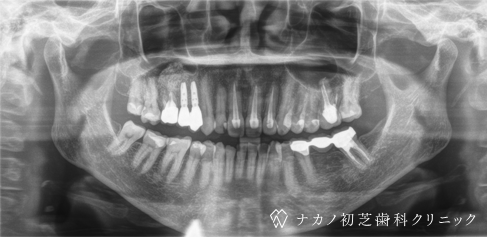

インプラント・4本 (60代女性)

-

BEFORE

AFTER

年齢 60代女性

治療内容 インプラント治療4本(骨造成と歯肉移植の併用)

インプラント治療とは、歯を抜いた所にチタン製の人工歯根を埋入し、その上に歯を入れる方法です。骨と歯肉を増やすことで、より審美的に治療が出来ました。費用 1本 400,000円(税込 440,000円)

リスク・副作用

腫れ・疼痛・違和感を感じるなどの症状を生じることがあります。